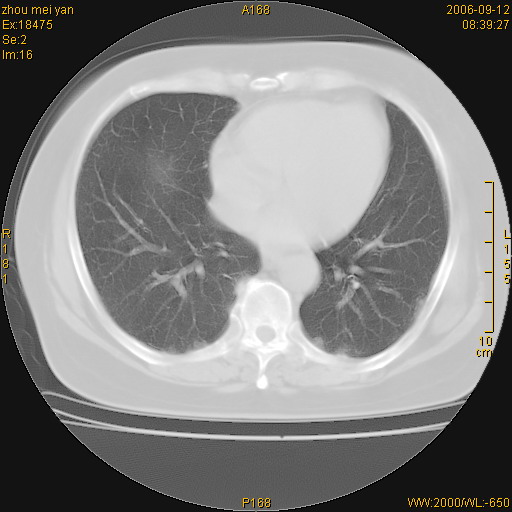

患者、女、55岁。因心率失常住院检查ct发现胸部多发结节。腹部b超肝、胆、胰、脾、肾、子宫附件未见异常。无结核病史,无粉尘接触史。请大家来会诊。谢谢!

病变位于胸膜,多发结节,边界清楚,内见小结节状钙化。其它未见异常。

双侧胸膜多发结节,形态不规则,边缘较清楚,每一个结节中心似乎都有钙化点的特征,与胸膜广基相切。临床无结核病史,无粉尘接触史。

影像表现十分有特点:双侧肋胸膜及膈胸膜广泛散在分布大小在2至6mm左右,较大病灶中心可见钙化。

考虑恶性胸膜间皮瘤可能性大,病灶位于胸膜,以宽基地与胸膜相连,呈结节样改变,部分病灶内可见点状钙化影。请各位老师多多指导!

双侧肋胸膜及膈胸膜广泛散在分布大小不等结节影,较大病灶中心可见钙化。